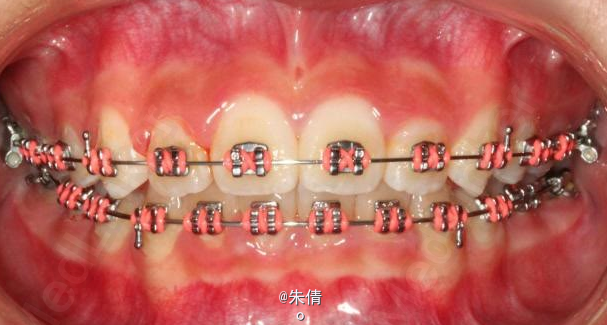

对于面型较好,拥挤度不大的病例,推磨牙向后不失为一种很好的方法,当然现在推磨牙后向的手段和方法很多,但是主要 是适应证的问题。我认为我们在做推磨牙向后,首先是考虑拥挤度,第二个要考虑的是现有的面型,第三点也是很重要的一点,是考虑牙弓后段拥挤度,Tweed-Merryfireld拥挤度的诊断方法将牙弓拥挤度分析分为三段,牙弓前段拥挤度,牙弓中段的拥挤度,以及牙弓后段的拥挤度。不管用什么方法或是手段推磨牙向后,一定不能将牙弓前端矛盾移到牙弓中段或是后段。今天给大家看一直面型,拥挤度不是很大推磨牙向后的病例。希望对大家能有所帮助。